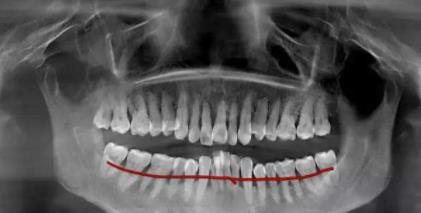

第二張拍片圖片如下:

從(cong) X線片可以看出,牙周病,牙槽骨廣泛吸收嚴(yan) 重,牙根之間的黑色區域就是黑色的,說明是空的,沒有骨頭,而如果是正常的牙槽骨條件,是不會(hui) 有黑色的,而是通常正常的牙槽骨應該在紅線以上,而且在紅線以下的牙根處應該是沒有黑色牙槽骨缺失的情況)。